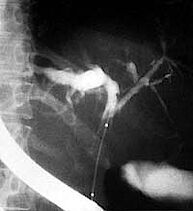

Die Ballondilatation wird bei der primär sklerosierenden Cholangitis (PSC) angewandt. Die PSC ist eine entzündliche Erkrankung der Gallenwege, die zu einem Nebeneinander von entzündlich- vernarbenden Engstellen einerseits und Gangerweiterungen andererseits führt [Abb. 1]. Durch die Engstellen im Gallengang kommt es zu einem Gallenaufstau mit Ikterus (Gelbsucht). Werden die Engstellen durch eine Ballondilatation aufgedehnt, kann ein ausreichender Gallefluss erreicht werden [Abb. 3]. Ballondilatationen von Engstellen der Gallengänge bei PSC wirken sich wahrscheinlich günstig auf das Fortschreiten der Erkrankung aus. Belegt wird dieses Vorgehen durch eine an der Universität Heidelberg durchgeführte Studie, die weltweite Anerkennung fand.

Die wichtigste Indikation nach einer Lebertransplantation ist die Aufdehnung von engen Gallengangsanastomosen. Bei einem Teil der Patienten kommt es kurz nach der Transplantation zu einer Unterversorgung des Gewebes an der Verbindungsstelle zwischen Transplantat und Gallengang des Empfängers. Diese Unterversorgung kann zu einer Engstellung dieser Verbindungsstelle führen [Abb. 5].